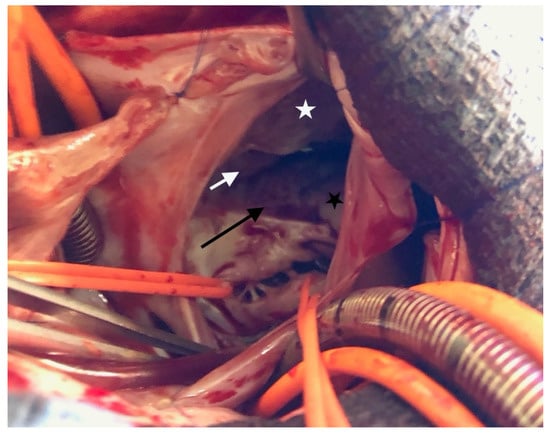

Echocardiography in a fetus at 25 weeks of gestation (WG) from a 19-year-old woman, without history of familial CHD, showed: (i) a typical partial common AVCD with a cleft on the left atrioventricular valve (AVV) without stenosis or leak and a large ostium primum atrial septal defect (ASD); (ii) Ebstein abnormality of the right AVV with a significant leak, causing a dilatation of the right atrium (RA) (Figure 1; Videos S1 and S2); (iii) “functional pulmonary atresia” with inconstant anterograde passage and (iv) retrograde flow in a tortuous ductus arteriosus. Other cardiac structures were normal. Cytogenetic analysis via amniocentesis had normal results. At 30 WG, moderate atrialization of the right ventricle and a pulmonary insufficiency were noted (Figure 2).

Figure 1. Four-chambers view: color Doppler: tricuspid insufficiency from the apex due to Ebstein’s anomaly.